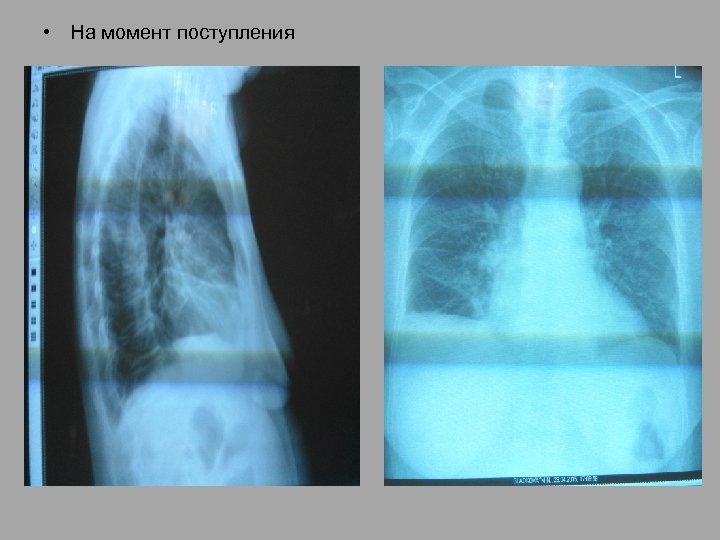

• На момент поступления

• На момент поступления в ОРИТ